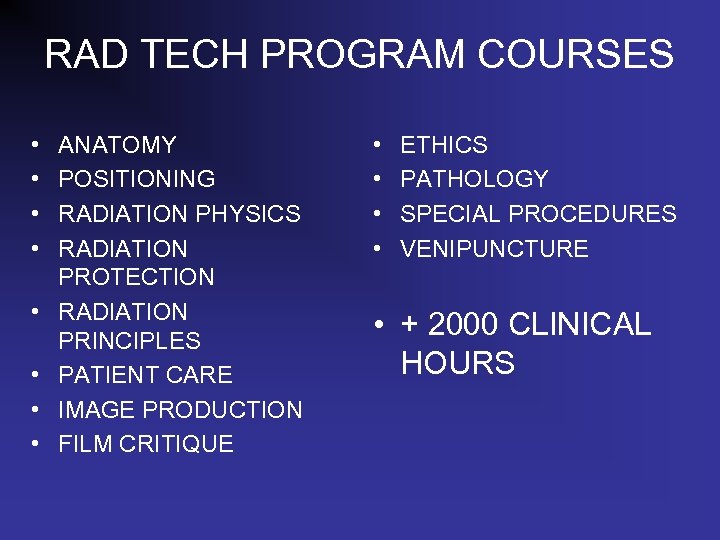

RAD TECH PROGRAM COURSES • • ANATOMY POSITIONING RADIATION PHYSICS RADIATION PROTECTION RADIATION PRINCIPLES PATIENT CARE IMAGE PRODUCTION FILM CRITIQUE • • ETHICS PATHOLOGY SPECIAL PROCEDURES VENIPUNCTURE • + 2000 CLINICAL HOURS

RAD TECH PROGRAM COURSES • • ANATOMY POSITIONING RADIATION PHYSICS RADIATION PROTECTION RADIATION PRINCIPLES PATIENT CARE IMAGE PRODUCTION FILM CRITIQUE • • ETHICS PATHOLOGY SPECIAL PROCEDURES VENIPUNCTURE • + 2000 CLINICAL HOURS